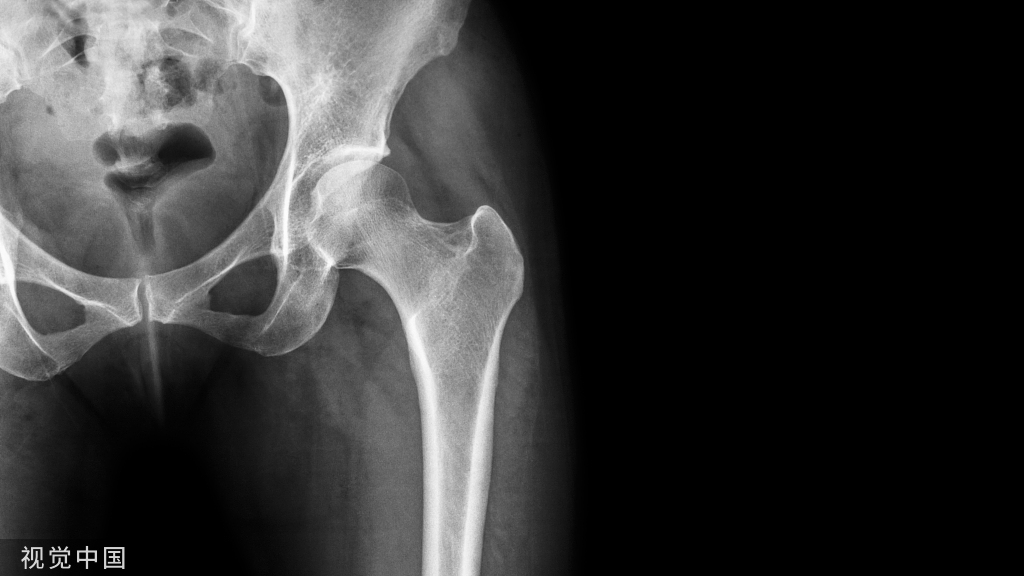

病例5股骨颈骨折,在CT横断面软组织窗上可见在髂腰肌内出现积脂血症表现。